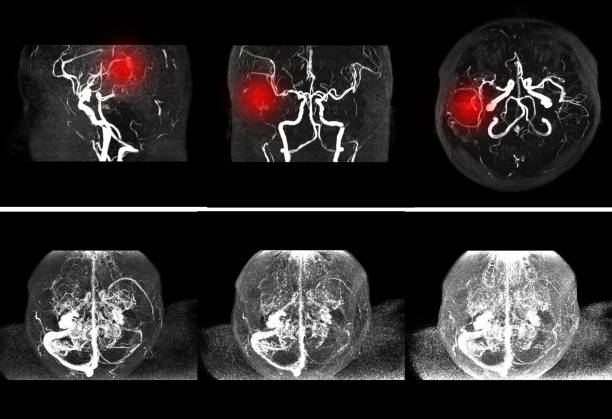

뇌경색 후유증은 심각한 장애를 남길 수 있는 신체적, 정신적 문제를 야기할 수 있는 중요한 주제입니다.

뇌경색 의심이 된다면 빠르게 대응해서 치료를 하는게 좋습니다.

뇌경색 후유증은 다양한 증상을 유발할 수 있습니다. 이러한 증상은 흔히 다음과 같이 나눌 수 있습니다.